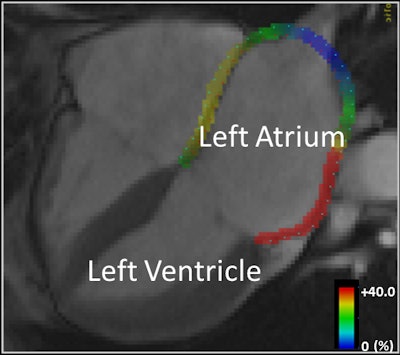

The MRI technique uses a 1.5-tesla MRI scanner (Magnetom Avanto, Siemens Healthcare) with semiautomated multimodality tissue-tracking (MTT) software (Toshiba America Medical Systems) to analyze cardiac muscle movement. The software was developed with the help of study co-author Dr. Joao Lima, who has published previous research using the MRI technique to assess left atrium function (Radiology, December 2014, Vol. 273:3, pp. 703-713).

In their review of motion and MR images, the researchers found that the left atrium of patients with a history of stroke or TIA was noticeably less able to empty blood from the atrium into the left ventricle. This so-called "conduit" function contributed an average of 35% of ventricular filling per minute in patients with a history of stroke or TIA, compared with 46% per minute among the control subjects.

In addition, the left atria were larger in patients with a history of stroke or TIA, with an average volume of 52 mL/m2, compared with 44 mL/m2 in the control group. Also, the left atria of patients with a history of stroke or TIA had worse overall ability to contract with each heartbeat (booster pump function), meaning that the heart muscle was less elastic and less able to account for strain.